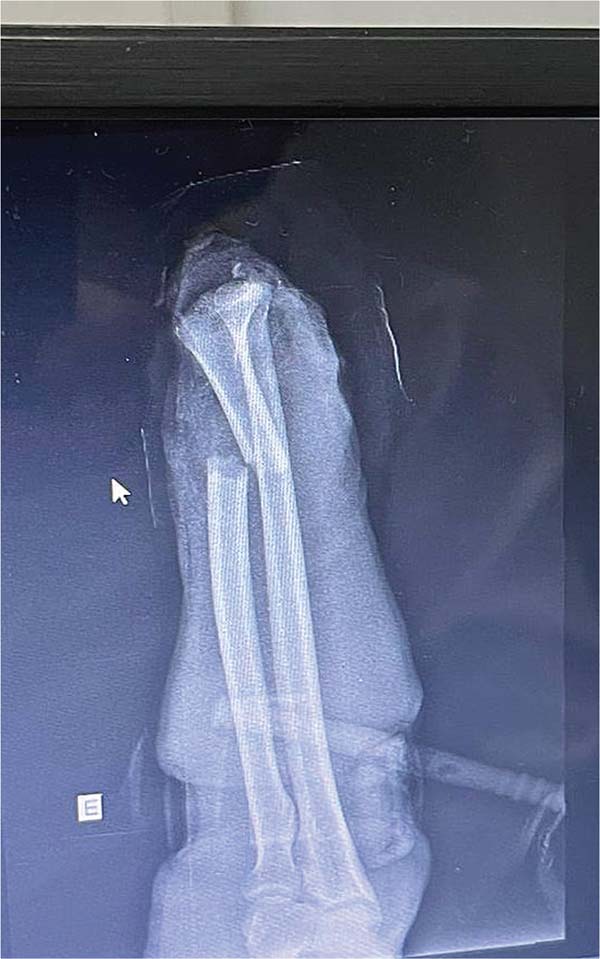

A 56-year-old patient (IPB), male, married, born and living in Fortaleza, was admitted to the hospital following an accident involving a saw in a butcher shop. He presented with a total amputation of his left hand at the wrist level with bone and tendon exposure. The patient arrived with a tourniquet on his left arm and his amputated hand in an ice-filled contain-er. He reported that the accident had occurred approximately 40 minutes before. On examination, he was stable but mod-erately pale due to significant blood loss, with no loss of consciousness, and a heart rate close to 110 bpm, indicating grade 2 hypovolemic shock. There were no signs of abrasions or trauma to other limbs (►Figs. 1-3).

After initial measures according to the Advanced Trauma Life Support (ATLS) protocol, we performed the following surgical steps: vascular stump dissection with identification of the radial and ulnar arteries, and the ulnar and median nerves; heparinization of the blood vessels of the amputated extremity; bone fixation of the radius and wrist block with Kirschner wires; primary microvascular anastomoses of the radial and ulnar arteries and three dorsal veins; suture of the median and ulnar nerves under microscope guidance; and, finally, an en bloc flexor tenorrhaphy and skin grafting over the wound due to tissue loss (►Figs. 4-7).4